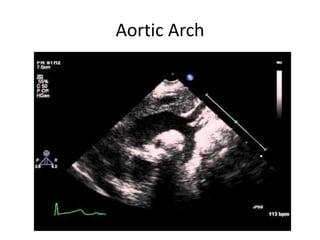

This echocardiogram report describes various views of the heart including the short axis, long axis, and four chamber views. It notes findings such as a right aortic arch, right pulmonary artery with thrombus, and transposition of the great arteries. The report also discusses acoustic windows, the aortic arch, ductus arteriosus, and mitral Doppler imaging.